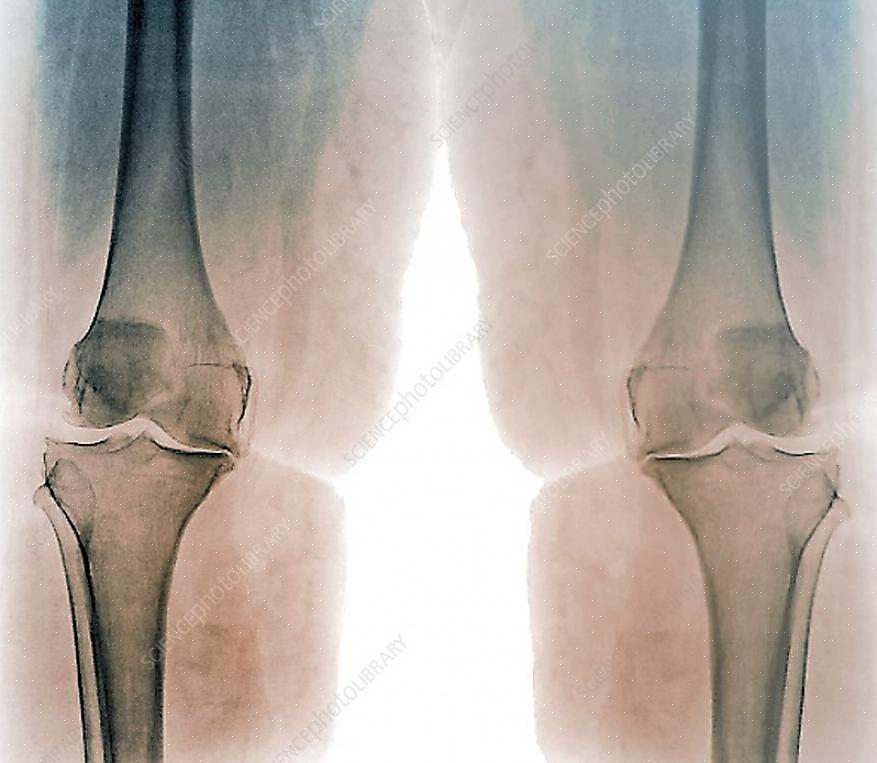

ארתרוזיס היא הפרעה ראומטית המתפתחת כניוון של הסחוס המפרקי. זוהי מחלה של המפרקים הנפוצה מאוד בקרב קשישים ולעיתים קרובות פוגעת במפרקים מסוימים. זהו המקרה של דלקת מפרקים ניוונית בברך, אחד המפרקים הפגיעים ביותר של הגוף.

דלקת מפרקים ניוונית בברך: גורמים ותסמינים

התסמין העיקרי הקשור לאוסטאוארתריטיס בברך הוא כאב, הנמשך גם במנוחה. כאשר אנו מתחילים בפעילות גופנית, אי הנוחות מוותרת למספר דקות, אך חוזרת בהדרגה עם הפעילות.

תסמינים אחרים כוללים נוקשות, חוסר תחושה ועקצוצים במפרק, עיוות של המפרק ולבסוף, אובדן תפקוד. ובכל זאת, כאב חריף הוא הסיבה העיקרית לכך שאנשים הסובלים מדלקת פרקים מוצאים אותו כמעט בלתי נסבל. לכן חולים צריכים להתייעץ עם מומחים כדי למנוע ולטפל במצב זה.